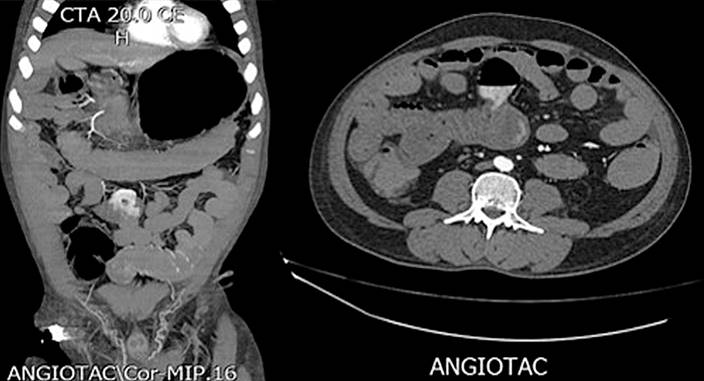

During the first three days of hospitalization, he persisted with hematochezia, hypotension, and severe anemia that did not correct despite being polytransfused. So, a mesenteric arteriography was requested, in which no lesions were found to explain the bleeding. The patient became hemodynamically unstable, for which he was transferred to the intensive care unit (ICU), requiring transfusion, vasopressor support, and invasive mechanical ventilation. In addition, he had a picture of hematemesis requiring upper digestive tract endoscopy that reported “angiodysplasia of the duodenal bulb, which received sclerotherapy.” Due to the persistence of hemodynamic instability, lower gastrointestinal bleeding, and severe anemia, an abdominal CT angiography was performed, which revealed a “dilation in the ileal small intestinal segment, which could correspond to a Meckel’s diverticulum, with extravasation of the contrast medium through this segment” (Figure 1). Then, a selective embolization was performed using arteriography (Figures 2 and 3).

Figure 1 Computed axial tomography showing a thin-walled cystic structure with an air-fluid level corresponding to a jejunal diverticulum. Source: Radiology Service, Hospital Comuneros. Selected by the authors.